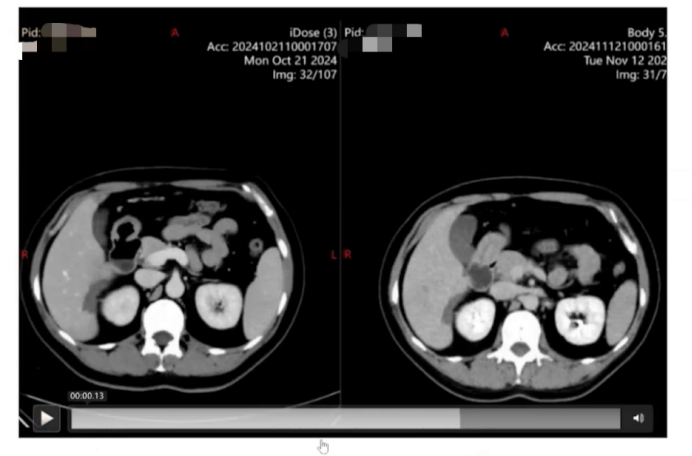

胸部CT:双肺多发微结节;腹部CT:提示肝右叶片状稍低密度影(4.2cm×5.6cm),肝脓肿可能。

经验性给予甲硝唑、米诺环素和头孢曲松治疗,覆盖院外未覆盖的可能病原体,同时复查腹部CT,显示肝右叶片状稍低密度病变较前增大,遂再次行经皮肝穿刺引流,送检肝组织NGS化验,但结果未提示特殊病原体。初步考虑肝内感染指标阴性,结核、真菌相关检查阴性,寄生虫相关化验再次复查也无阳性结果。免疫方面,ANCA斑点法1:160阳性,但ANCA阴性,过敏原因无特殊提示。肿瘤方面,外周血涂片提示嗜酸性粒细胞升高,未见到异型细胞,肿瘤标志物CA724轻度升高,其他包括AFP均为阴性。

追问患者流行病学史,患者有食用凉拌蔬菜情况,且曾长期在外卖平台购买泰国菜,多为蔬菜沙拉。明确诊断后,给予特效药三氯苯达唑治疗,患者服用两天后体温持续正常,稳定1周后出院。出院后随访,嗜酸性粒细胞呈进行性下降趋势,体温保持稳定正常,腹盆CT复查显示病灶缩小。